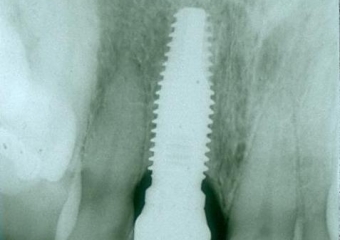

Rx do implante com a prótese instalada.